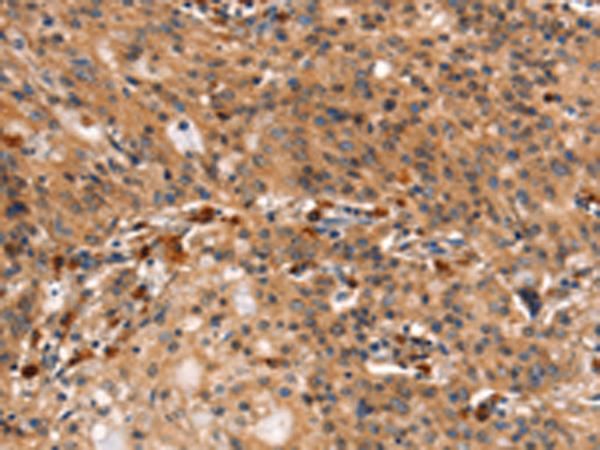

分类: 科研抗体货号: P11195别名: APO-CIV; APOC-IV应用: IHC反应种属: Human